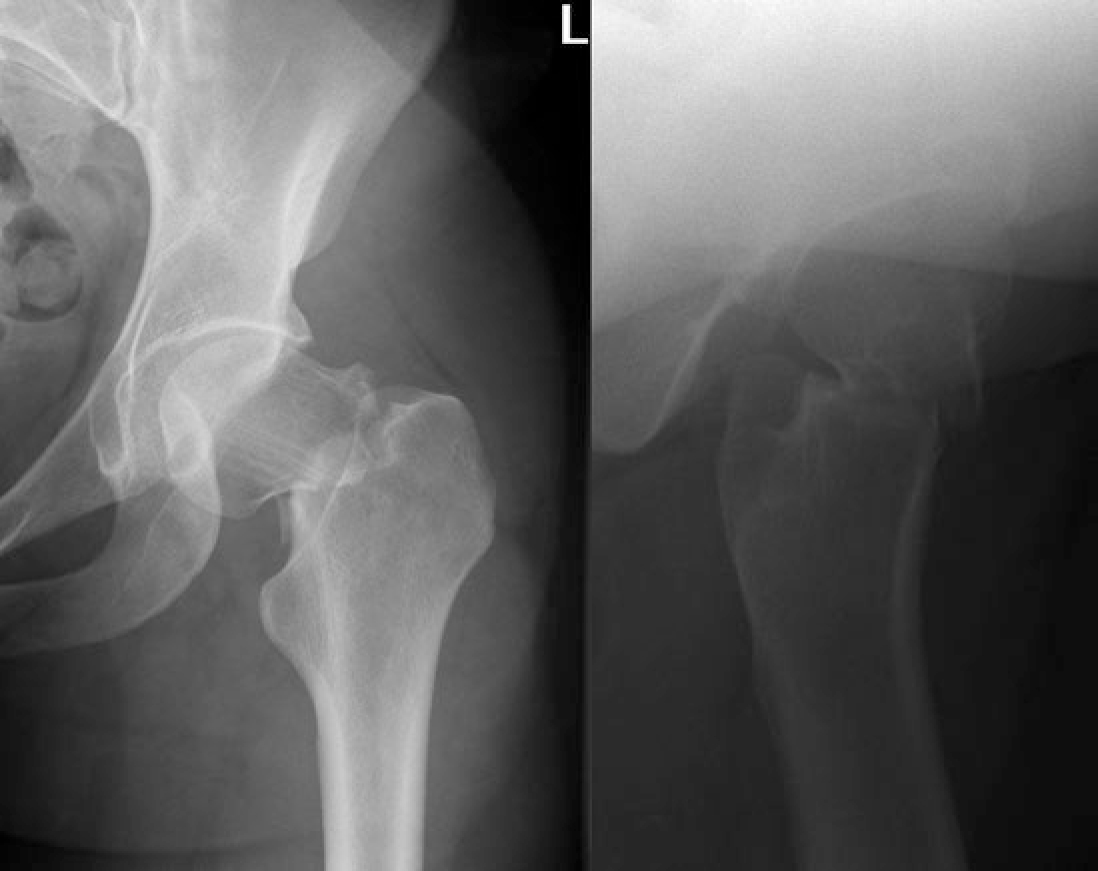

Meestal ontstaat het letsel door een val waarna steunname op het aangedane been zo goed als onmogelijk is. De belangrijkste symptomen van een barst of breuk in de hals van het dijbeen stressfractuur femur zijn een vage pijn ter hoogte van de lies bij belastende activiteiten. Een marsfractuur bevindt zich in de voorvoet met name rond het 2e 3e 4e middenvoetsbeentje.

Een dergelijke stressfractuur wordt vaak gemist kan catastrofaal aflopen en is meestal het gevolg van langdurige schokbelasting zoals bij langeafstandslopers. Mensen met een verhoogd risico op stressfracturen zijn militairen atleten dansers personen die onlangs startten met intensieve training en personen die zware wandel- of hardloopoefeningen doen terwijl ze dat niet gewoon zijn Een fractuur. Gezien fietsen goed gaat beweegt de heup wel goed maar als er lichaamsgewicht op komt wordt het moeizamer.

Stressfractuur Van De Femurhals Bij Een Marathonloopster Huisarts Wetenschap